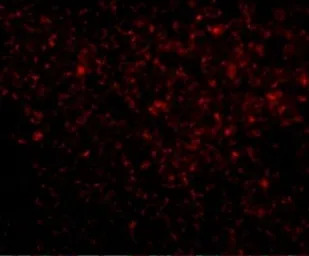

IHC-P analysis of human spleen tissue using GTX31367 TREX1 antibody.

Working concentration : 20 μg/ml